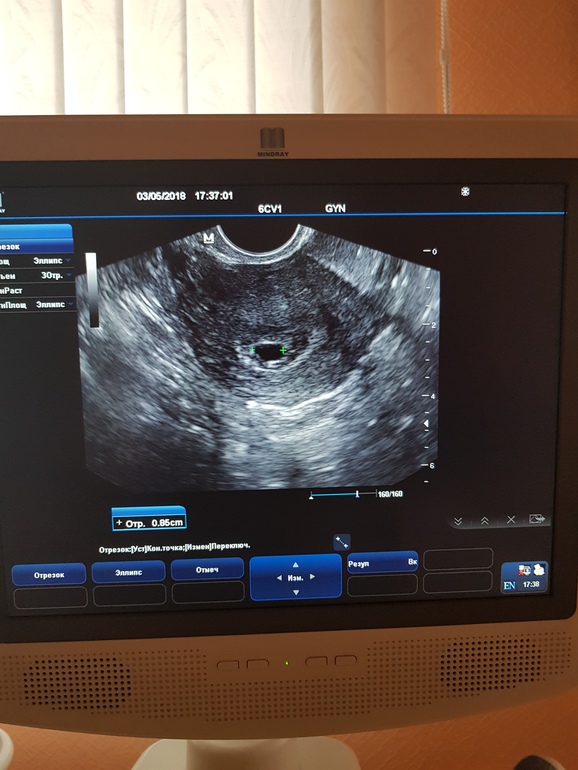

Здравствуйте! К 5 неделям беременности диаметр плодного яйца примерно 1 см как изображено на Вашей фотографии. Однако диагноз беременность ставится на основании анамнестических данных; задержка менструации, тест на беременность ,осмотр специалиста, анализ крови хгч, заключение ультразвукового исследования (фото с заключением) . Так же перед планированием и во время беременности рекомендуется принимать витаминно-минеральные комплексы содержащие оптимальную дозу фолиевой кислоты. Однако, перед применением того или иного препарата Вам необходимо проконсультироваться со своим акушер-гинекологом, т.к на рынке представлены различные препараты содержащие фолиевую кислоту, например Элевит.